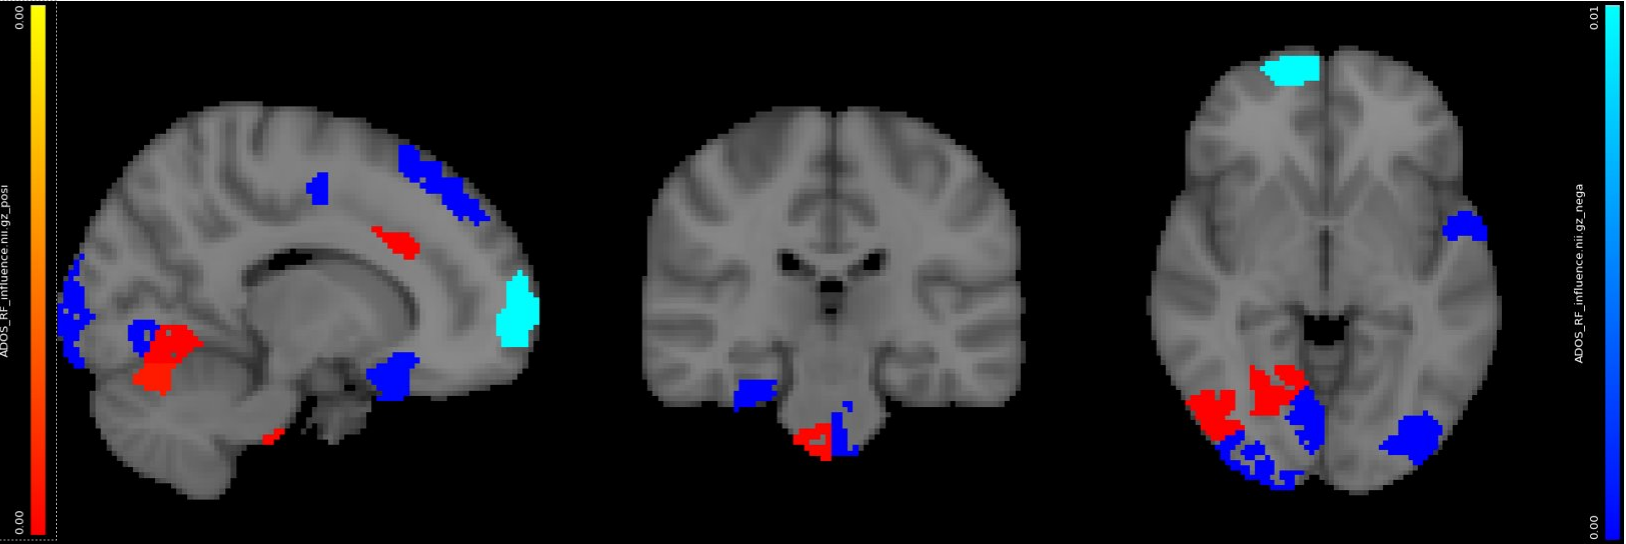

(c) Voxel-level random forest model for standardized ADOS

For standardized ADOS score, the best result in literature achieves r=0.51 between predictions and measurements with 156 subjects based on cortical thickness [17]. Our model achieved r=0.50 with 19 patients (Fig. 6(c)) based on fMRI.

Neurosynth decoder results (Fig. 9(d), Fig. 10 right figure) show that selected regions match the literature [11]. The selected regions are slightly different across experiments due to different tasks, datasets and target measures. Many regions are shared across experiments, such as prefrontal cortex and visual cortex.